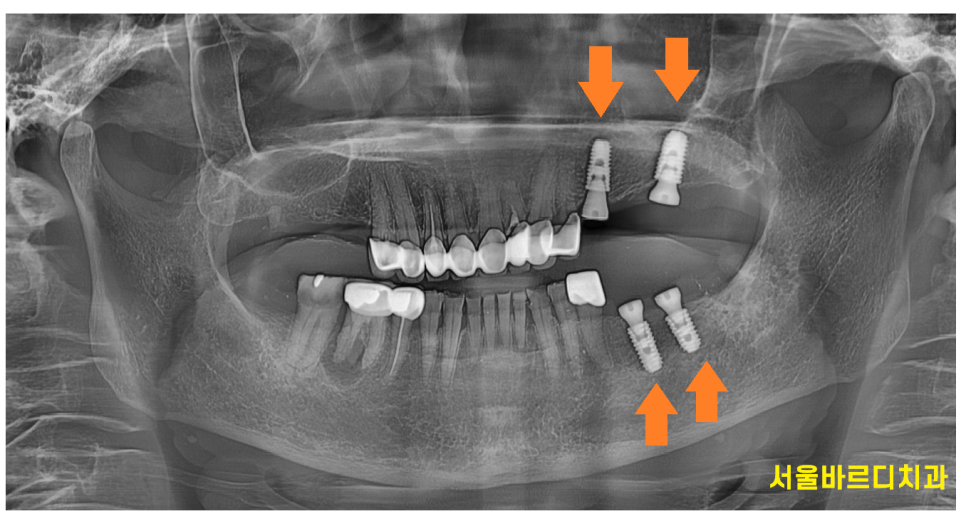

위 아래 임플란트를 왼쪽부터 1차 진행

한달 뒤 오른쪽 임플란트 수술을 진행했습니다.

230829

오른쪽 수술을 마친 직후입니다.

240202

딱 5번 내원하셔서 치료를 끝내드렸습니다.

24.2.2

이가없던 위 어금니도

문제가 있던 아래 어금니도

문제가 있는 부분 싹 고쳐드렸습니다.